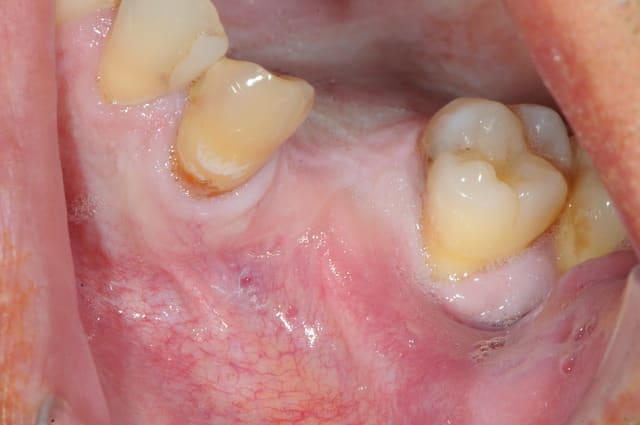

en attendant voici un des deux sinus de ce matin.

MP3 ( chez Pred) en comblement et ROG avec membrane et pins pour palier la forte concavité vestibulaire.

ps: je mets ces photos surtout parce que c'est rigolo de demander au patient de faire bouger sa membrane sinusienne...